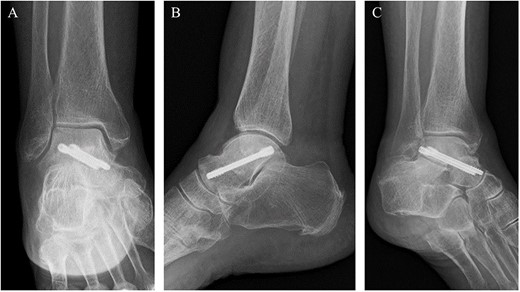

A 76-year-old female, who worked as a cleaner, complained of pain in her right ankle when going downstairs while working. She had medical history of only osteoporosis and had taking daily active vitamin D for >10 years. She was given conservative treatment for 1 month at a local clinic, however, her ankle pain persisted and so she visited our clinic. Physical examinations revealed tenderness and swelling at the anterior aspect of the ankle. Plain radiographs showed no obvious abnormal findings (Fig. 1). Magnetic resonance imaging (MRI) revealed a low signal linear line in the talar neck and a bone marrow edema around the line (Fig. 2). Non-contrast computed tomography (CT) demonstrated an obvious fracture line in the talar neck, however, the bone fragment was not displaced (Fig. 3). Based on medical histories, clinical and radiological findings, we diagnosed her with a fragility fracture of the talar neck associated with osteoporosis. Because the patient was elderly and it was difficult to treat using a prolonged non-weightbearing cast, we applied operative treatment to allow early rehabilitation. The operation was performed under spinal anesthesia in a prone position with an air tourniquet and a fluoroscopy. The posteromedial and posterolateral portals were created according to van Dijk et al. [10]. First, the posterior aspect of the talus was observed using a 4.0-mm diameter 30° arthroscope, and soft tissues around the talus (including synovium and adipose tissues) were removed with a 3.5-mm diameter motorized shaver. After confirming the posterior part of the talar body and the FHL, two 1.6-mm diameter guidewires were parallelly inserted from the posterior part of the talar body to the talar head by hindfoot endoscopy and fluoroscopy (Fig. 4A), and two cannulated 4.5-mm diameter double-threaded screws (Double Thread Screw, Meira, Nagoya, Japan) were inserted through the guidewires (Fig. 4B). The wound was sutured, and the operation was concluded (Fig. 5). Active range of motion exercises were allowed immediately after surgery, and a non-weightbearing short leg splint was worn for 1 week. Partial-weight bearing was permitted at 2 weeks and full-weight bearing was permitted at 4 weeks post-operatively. In addition, daily injections of teriparatide (Forteo, Eli Lilly and Company, Indianapolis, IN, USA) were introduced 2 weeks post-operatively. Eight weeks after the operation, the patient was able to return to work without pain or functional impairment. One year postsurgery, the patient was still working as a cleaner without any symptoms or complications.

Post-operative plain radiographs revealed that two cannulated 4.5-mm double-threaded screws were inserted from the posterior part of the talus to the talar head as seen from the (A) anteroposterior, (B) lateral and (C) oblique views.